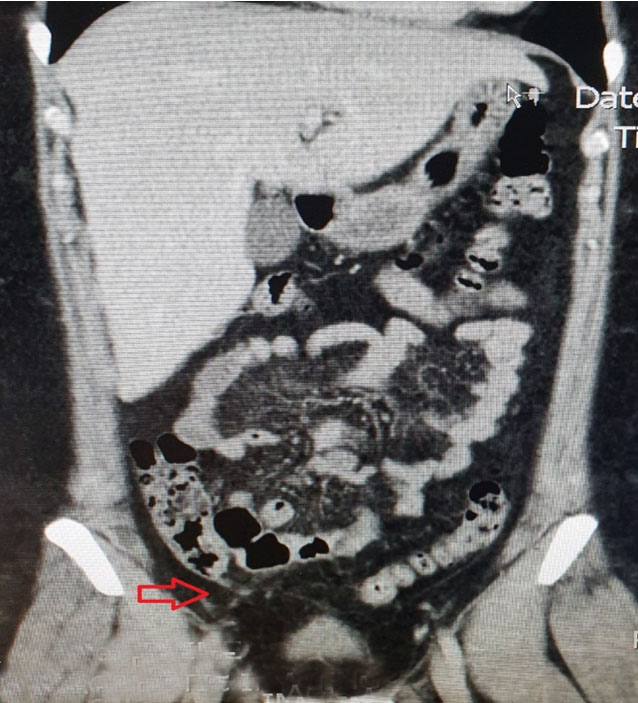

A pelvic ultrasound was done which revealed a possibility of a bicornuate uterus and a 4.4 cm mass seen within left ovary which is hypoechoic in nature which probably represent endometrioma (Figure 1). There was no free fluid noted or any adnexa mass seen. The appendix was not visualized. Due to her nonresolving abdominal pain, a CT scan of abdomen and pelvis was done. It was noted on the scan that there was an inflammatory change in the distal ileum with the appendix being slightly dilated at 6.3 mm and could suggest an early appendicitis (Figure 2 and Figure 3). Apart from the left ovary cyst there were no other abnormalities noted.

Figure 1: Ultrasound of the left ovary showing width of 4 cm.

Figure 3: Coronal view of the CT scan: red arrow indicates the slightly dilated appendix at 6.3 cm with inflammatory changes in the distal ileum.